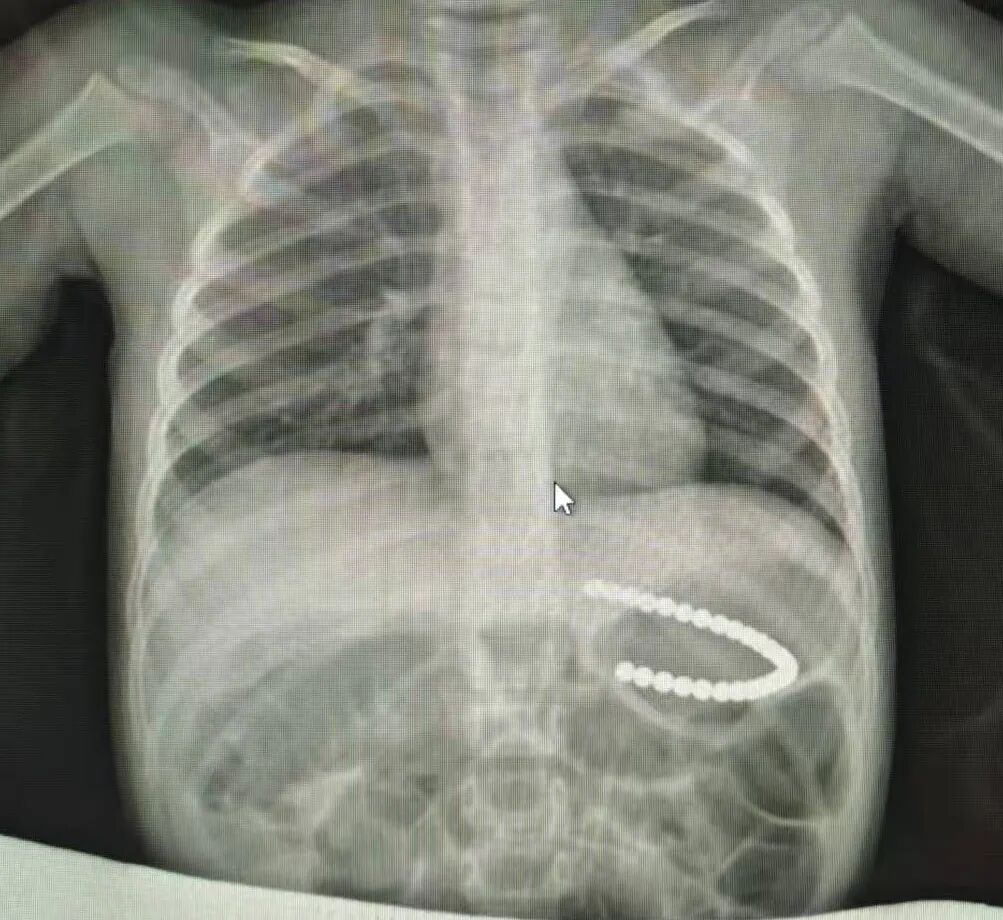

当日19时许,患儿到达医院,李忠赶紧带着患儿去做X光片,患儿磁力珠的位置仍然在胃里。麻醉前需要禁食水,询问患儿了解刚食用晚饭,联系消化内科专家,决定第二日胃镜下取出。

1月26日10时许,李忠带患儿再次拍片,发现磁力珠大部分已到十二指肠,少部分在胃里。按照李忠制定的手术方案,患儿在手术室进行全麻,先由消化内科医生通过胃镜对患儿取磁力珠,如无法取出,李忠将带领医疗团队给予腹腔镜手术,第三个方案则是行开放手术。而患儿这么小,开放手术创伤太大,谁也不想采取第三个方案。